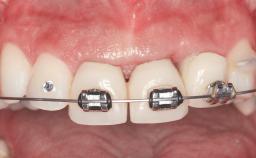

Replacement of Four Incisors with a Fixed Partial Denture on Two Narrow-Neck Implants after Implant Failure

| # of Teeth | 4 |

| Prosthesis Type | FDP |

| Provisional Implant-Supported Prosthesis | Prosthodontic margin >3 mm apical to mucosal crest Prosthodontic margin >3 mm apical to mucosal crest |